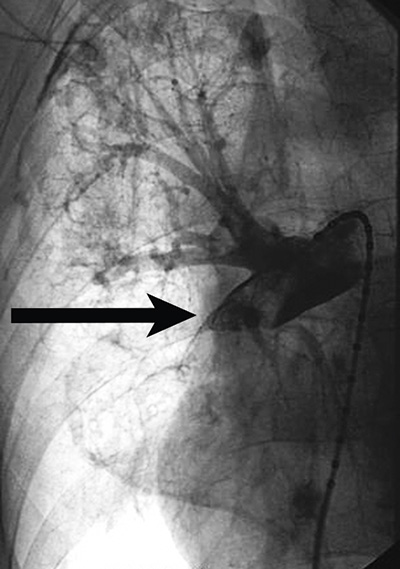

Avlägsnande av främmande kroppar från lungcirkulationen, t ex bitar av katetrar, är ett välkänt interventionellt ingrepp, liksom placering av filter i vena cava. Vena cava-filter förhindrar lungemboli hos riskpatienter, som inte kan behandlas med antikoagulantia och/eller inför kirurgi som kräver långvarig postoperativ immobilisering. Nya typer av filter kan avlägsnas efter upp till 180–270 dagar om de inte längre behövs. Interventionell behandling av pulmonella embolier med embolusfragmentering och -aspiration är prövad [13], men en i Sverige ännu inte allmänt accepterad metod (Figur 4). Även behandling av benigna förträngningar i lungartärer med ballongdilatation visar lovande resultat [14].

Figur 4. Behandling av lungemboli. Övre bilden visar stor embolus i högra underlobens artär. Undre bilden visar förbättrat blodflöde efter embolusfragmentering och -aspiration med interventionell radiologi.